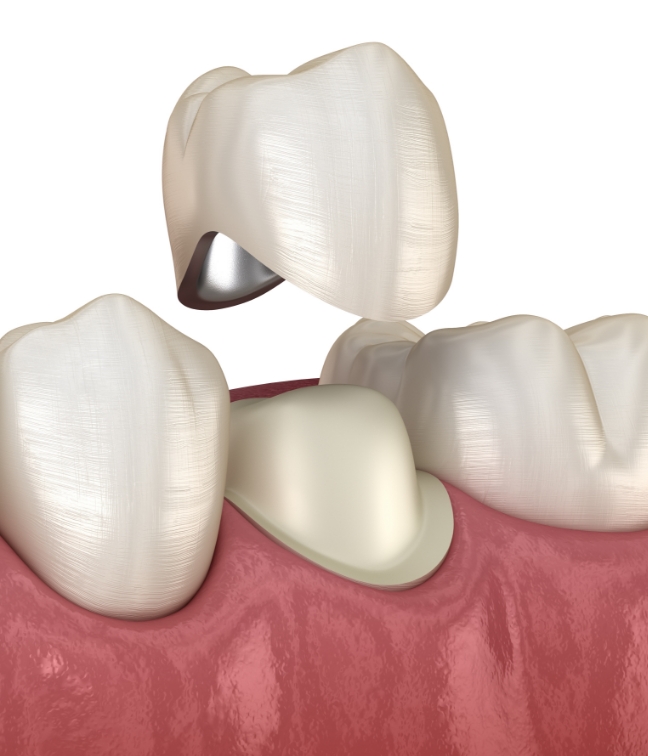

신경치료 후 약해진 치아를 전체적으로 감싸

보호하는 방법으로,

손상된 치아의 기능을

회복시키고 심미적인 부분까지

함께 개선할 수 있는 보철 치료입니다.